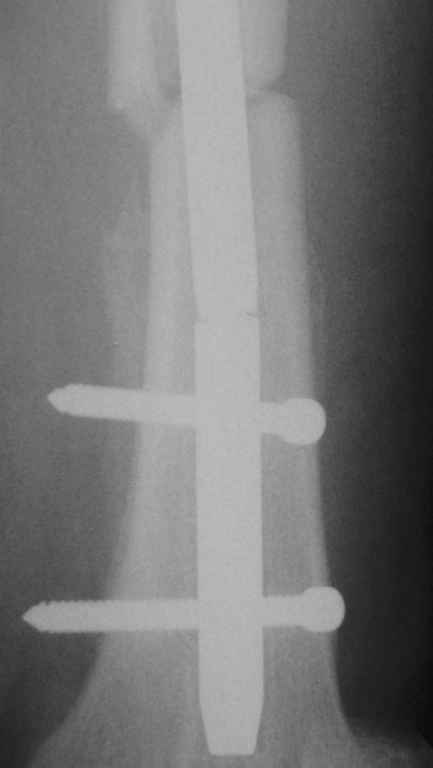

Перелом интрамедуллярного гвоздя

Уважаемые коллеги,Пациентка 40 лет, 6 мес назад был произведен интрамедуллярный синтез бедра канюлированным гвоздем без рассверливания. Обратилась в связи с появлением болей в бедре.

На Р-контроле – перелом гвоздя как следствие отсутствия динамизации конструкции (пациентка не обращалась в отделение). Планируем интрамедуллярный реостеосинтез с рассверливанием, однако возник вопрос о способе удаления дистального фрагмента гвоздя: с одной стороны – не хотелось бы беспокоить область перелома (разъединять отломки), с другой – лезть через колено-тоже не очень. Есть ли какие другие методы (удаления м/к) в данном случае?

1. сломанный стержень